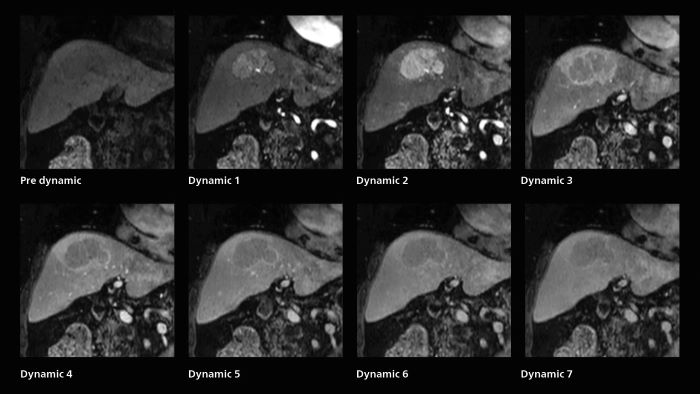

Dynamic MRI of liver using SmartSpeed

A patient was referred for MR imaging of HCC. A double arterial volume dynamic study was performed. Since it is a volume dynamic study, it can also be evaluated using MPR images. Performed on Elition X.

Fast dynamic liver MRI: volume dynamic study of 1.05 min, 1.6 x 1.8 x 2.0 mm, 200 slices

The hospital’s routine ExamCard for dynamic MRI of the liver uses total scan duration 1:05 min, dynamic scan time 9.2 sec, 1.6 x 1.8 x 2.0 mm, 200 slices, acceleration factor 8.